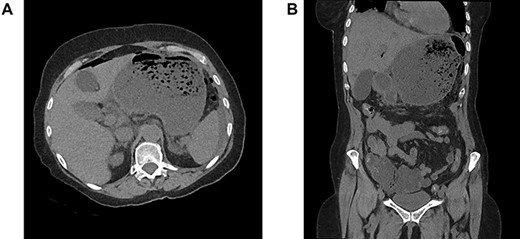

A 64-year-old woman was admitted in emergency for severe abdominal superior pain, nausea, dysphagia and fever. She explained having undergone a Nissen fundoplication 2 weeks earlier at another hospital, complicated a few days later by persistent dysphagia leading to redo-laparoscopy. Past medical history included hypertension, chronic obstructive pulmonary disease, hypothyroidism and appendectomy. On physical examination, she was septic (38.2°C, 110/70 mmHg, 110 bpm) with diffuse abdominal guarding. The blood test revealed a high grade of inflammation (C-reactive protein 17.35 mg/dL, white blood count 20.9 1000/mm3, lactic acid 3.2 mmol/L). The computed tomography scanner showed signs of perforation with hugely dilated stomach (Fig. 1A and B). Laparoscopic exploration attested to a generalized purulent peritonitis. Surprisingly, we found also a gastric greater curvature plication leading to a pyloric obstruction (Fig. 2A and B). Dismantling the Nissen wrap and the gastric plication allowed to find the gastric perforation on the top of the wrap (Fig. 3A and B). Simple closure of the perforation and large peritoneal lavage were performed. Postoperative recovery was marked by a left subphrenic abscess resolved under antibiotherapy. The patient was discharged on postoperative day (POD) 22.

(A) Nissen wrap, (B) gastric perforation on the top of the wrap.